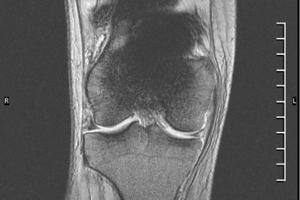

Secuencias para evitar Artefactos Ferromagnéticos

En ocasiones los pacientes con prótesis metálicas necesitan realizarse una Resonancia Magnética (MRI).…